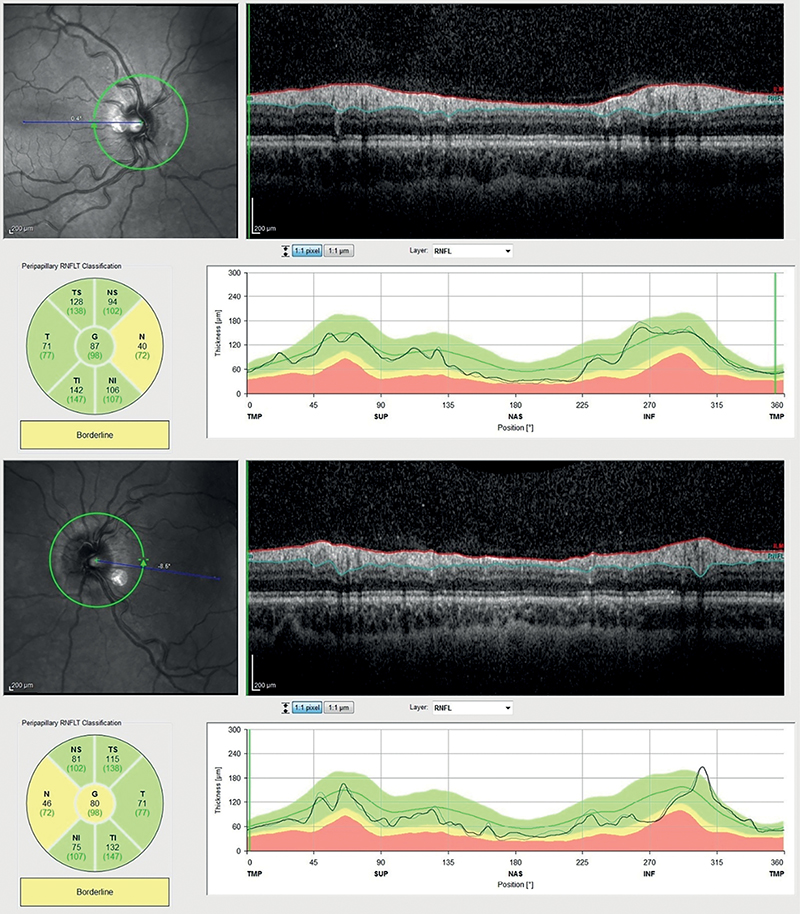

A tünetek és jelek alakulásából arra is következtethetünk, hogy a panaszok megszűnését követően is tartósan fennálló, lassan mérséklődő ödéma a panaszok jelentkezését is több nappal megelőzően indulhatott fejlődésnek, a doxycyclin szedésének befejezését követő 5 féléletidőn (100 óra) belül. Szintén az ödéma az észlelt panaszokat hosszan megelőző kialakulására utal, hogy betegünk első jelentkezésekor a mindkét oldalon megfigyelhető jelentős (2D/3D) prominentia ellenére csak bal szeme látóterében észlelt homályról számolt be. Jelenleg a 24 héten át fenntartott oralis acetazolamid terápia teljes elhagyását követően a beteg tartósan panaszmentes, korrigált látóélessége továbbra is mindkét szemen 1,0, látótere normalizálódott, a papillaödéma pedig mindkét oldalon tartósan megszűnt. A hosszan fennálló ödéma utóhatásának tekinthető a retinalis idegrostréteg (RNFL) mindkét oldali, nasalis kvadránsokban, OCT-vizsgálattal mérhető elvékonyodása, és a korábban fennálló ödéma aszimmetriájának megfelelő, bal oldalon alacsonyabb mérési értékek (3. ábra). Betegünk jelenleg a látóidegrost-veszteség ismeretében neuroprotektív céllal topicalis brimonidin monoterápiában részesül – szemnyomása ezen kezelés mellett ismételt mérésekkel igazoltan normál tartományban van. Fontos adalék, hogy a beteg szigorú diéta követésével kezelése ideje alatt 14 kilogramm testsúlycsökkenést is elért, ami feltehetően jelentősen hozzájárult a papillaödéma egyenletes mérséklődéséhez és megszűnéséhez.